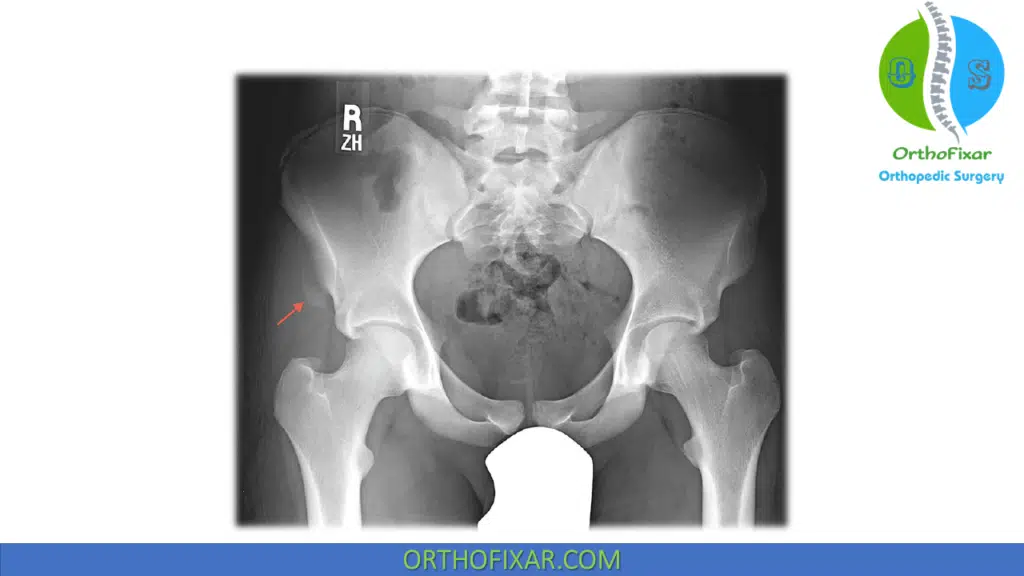

Radiographs is used to rule out fracture of the ilium.